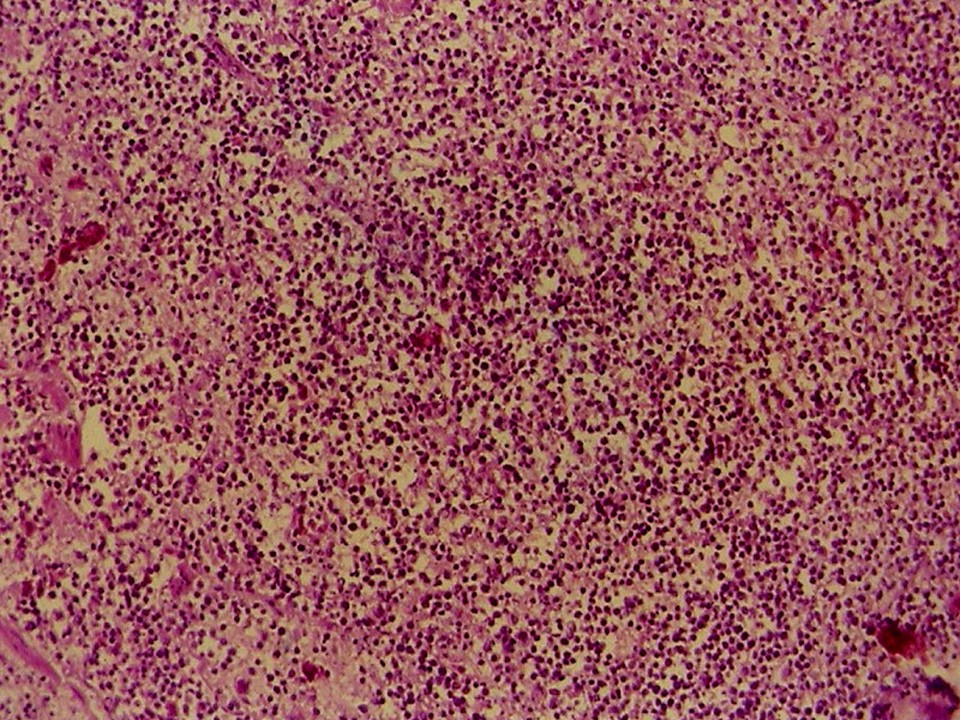

疾病中文名稱:馬立克病

疾病英文名稱:Marek's disease

影像說明:翼神經受侵犯而翅膀下垂,坐骨神經受侵犯呈劈腿狀